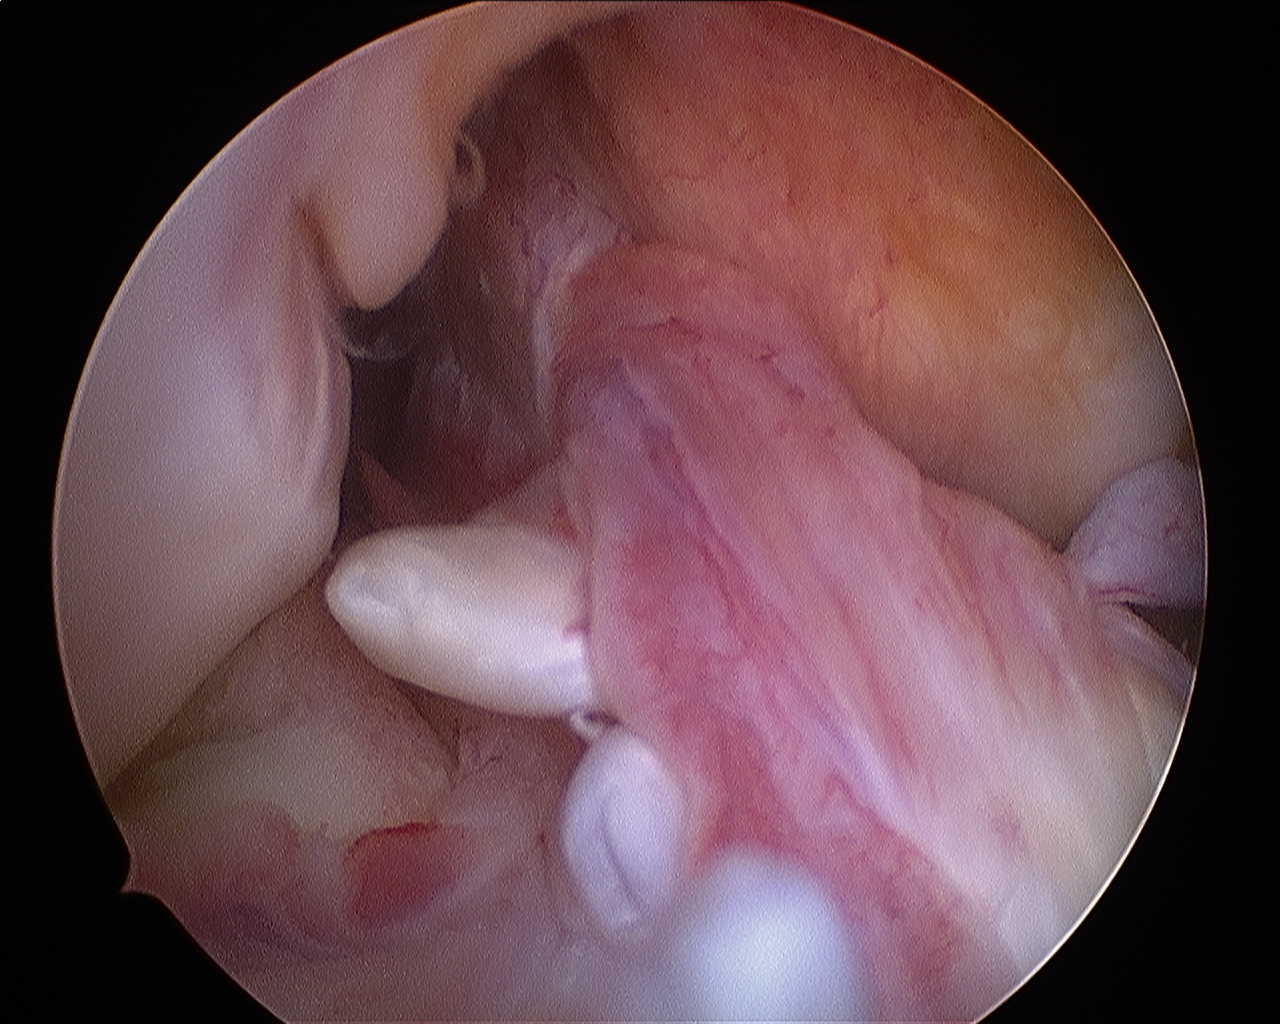

it’s a gold standard treatment of ACL tear whereby the torn ACL is replaced by a four or six fold graft taken from patient himself and reconstructing it to the place of original ACL using bone tunnels , it makes the knee joint stable again and helps in preserving other parts and components of the knee joint from further damage

This treatment is specially indicated when ACL undergoes mucoid changes ( ACL tissues convert into jelly like substance and impinges the intercondylar notch ) , there in this treatment the Knee arthroscopy is done to debulk the mucoid ACL and bony notchplasty of lateral femur condyle is done to avoid pain secondary to notch stenosis – Several Scientific papers have proved that Decompression of acl and the notchplasty is the gold standard treatment of ACL mucoid whereby the conservative treatment have failed .